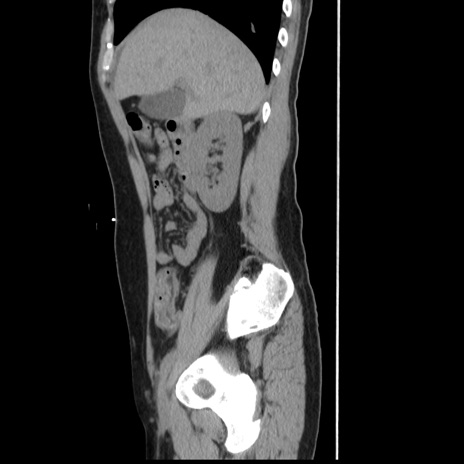

症例10(矢状断像)

【症例】 50歳代女性

【主訴】 腹痛

【現病歴】前日生レバーを食べた。今朝に排便あり。 昼前に突然発症の腹痛を生じ、当院救急外来を受診した。

【既往歴】 子宮筋腫にてで子宮全摘後

【身体所見】 意識清明、腹部:平坦、軟、下腹部やや左を中心に圧痛・反跳痛あり、筋性防御あり

【データ】WBC 7800、CRP 0.07